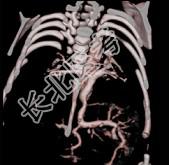

- 多项选择题女性,21岁, 活动后呼吸困难,时常发生上呼吸道感染, CT扫描如图所示,请选择正确的选项 ( )

A、考虑为肺静脉异位引流

D、该病人肺静脉异位引流入下腔静脉

E、该病人为心下型肺静脉异位引流